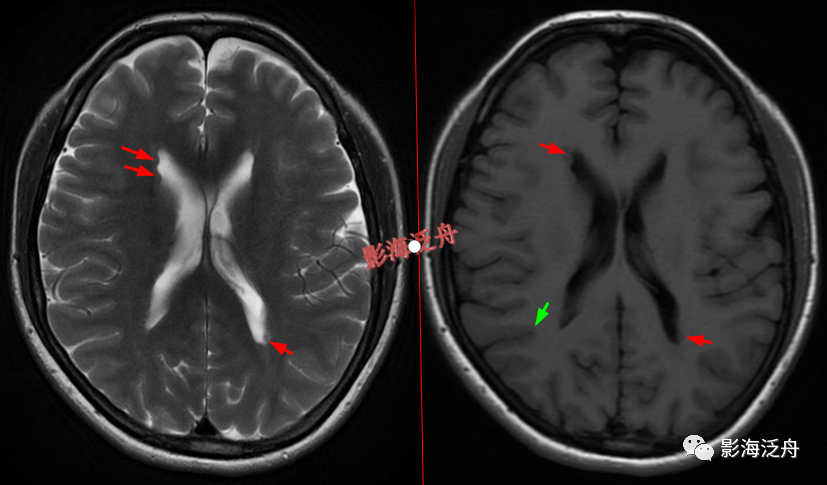

右侧侧脑室体部囊性占位(红箭),整体信号与脑脊液一致,病灶边缘部分显示,透明隔稍移位。

灰质移位,患者既往有癫痫病史。右侧侧脑室前角及左侧侧脑室后角可见异位的灰质结节(红箭),与大脑皮层下的灰质信号一致(绿箭),灰质异位患者多伴有癫痫症状。

透明隔缺如,我自己漏诊过的病例。上面有很多正常的图像可供对比观察。